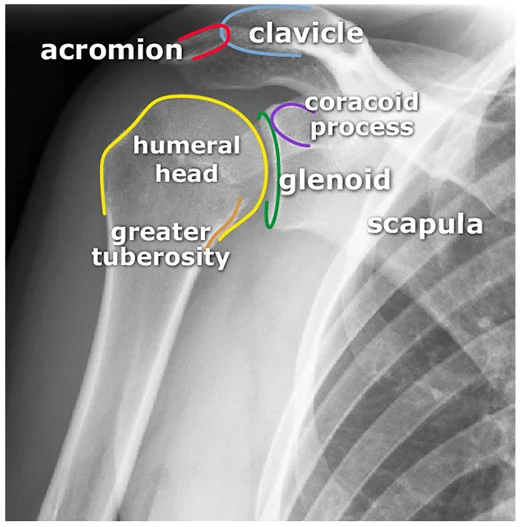

x-ray AP view of Shoulder Joint

- The image contains two X-ray views of a shoulder joint.

- The right X-ray is annotated with labels for various anatomical features.

- acromion

- clavicle

- coracoid process

- humeral head

- glenoid fossa

- greater tuberosity

- scapula